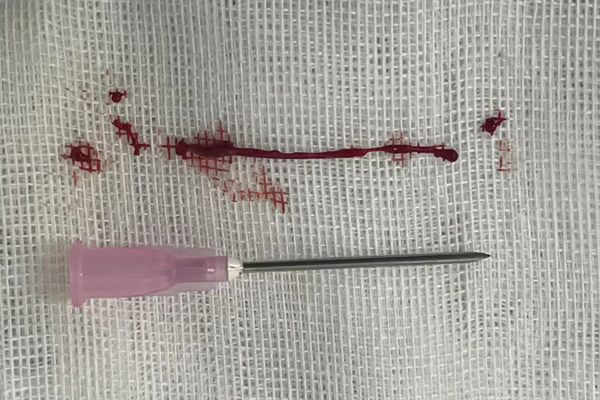

面对严峻挑战,救心团队最终不负所望,在冠状动脉抽出长达4厘米的血栓,并植入两枚支架。黄奶奶的心律即刻恢复正常,成功闯过鬼门关。进入导管室到导丝通过仅用时19分钟,DtoW 66分钟。